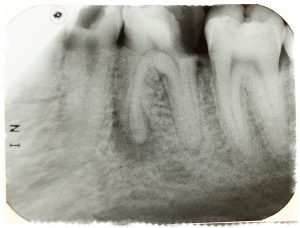

Периодонтит на корне зуба 36

Может произойти и так, что зуб ни когда не болел, но врач все же определил болезнь, которая называется периодонтит. Зуб может после лечения начать беспокоить. Лечение этого серьезного заболевания является достаточно сложной процедурой.

Периодонтит — это скопление различных микробов в костных тканях. Лечится оно только пломбированием каналов, которое закупоривает оставшиеся бактерии в корне зуба. После наложения пломбы организму, становиться, намного легче справляться с инфекцией. Но побочный эффект от такого лечения все же существует. Иногда может возникнуть не сильное воспаление или болевая реакция при нажатии на зуб. Это вполне нормальный ответ организма на постороннее вмешательство и волноваться не стоит, так как по истечении нескольких дней она проходит.